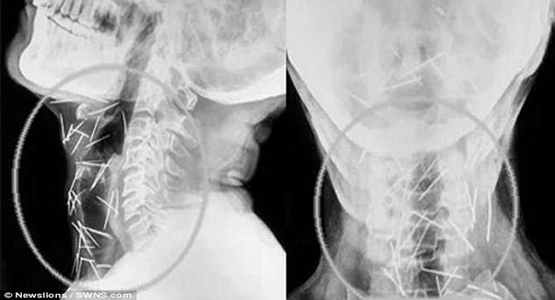

واضطر باديرلال مينا (56 عاماً) لزيارة 6 مستشفيات والخضوع لثلاث عمليات جراحية، لإزالة الدبابيس من ذراعيه وقدميه وعنقه، وحتى الآن تمت إزالة 91 دبوساً، البعض منها كان صدئاً للغاية، بعد أن تركت داخل جسده منذ عدة أشهر، بحسب صحيفة ديلي ميل البريطانية.

وأضاف الدكتور بارشار الذي أجرى العمليات الجراحية للمريض وفق ما اوردت شبكة ” 24 ” الإماراتية : “شكل إخراج الدبابيس من جسمه بأمان تحدياً كبيراً بالنسبة لنا، خاصة وأن بعضها كان مغروساً في الرغامى والمري، وحتى في الشريان السباتي الذي يحمل الأوكسجين إلى الدماغ”.